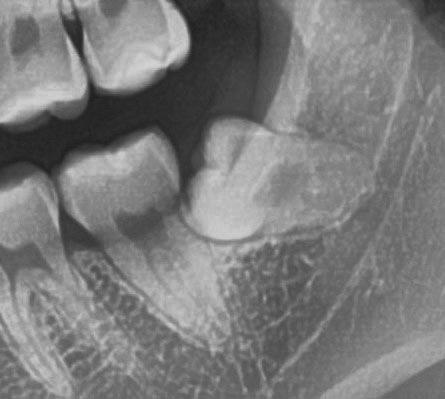

Dalla radiografia (Fig. 166) sembrava che il dente avesse due radici separate, quindi è stato eseguito un taglio orizzontale utilizzando il manipolo dritto per sezionare il dente a metà. Tuttavia, la corona si è frat-

turata poiché in realtà le radici erano unite e il dente non è stato sezionato completamente.